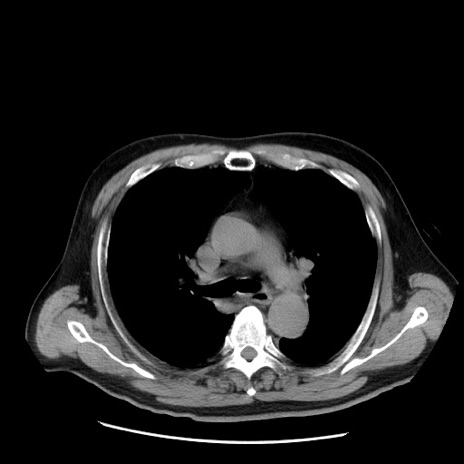

症例20(横断像)

【症例】 60歳代男性

【主訴】 腹部膨満、嘔吐

【現病歴】5日前頃より倦怠感を認め食事量減少し4日前の朝嘔吐、食事摂取困難となった。 3日前近医受診し点滴施行され整腸剤などを処方された。 当日他院を受診し、腹部膨満著明、炎症反応の上昇(CRP10.8、WBC11200)あり、紹介受診となる。

【身体所見】 意識JCS1 受け答えがはっきりしないBP 111/57mHg、 P 67bpm、、BT35.2°C、SpO2 97%(RA)、 腹部:膨隆、打診で鼓音あり、全体的に圧痛有り、腸蠕動音(-)、反跳痛ははっきりせず。

【データ】WBC 11400、CRP 14.20